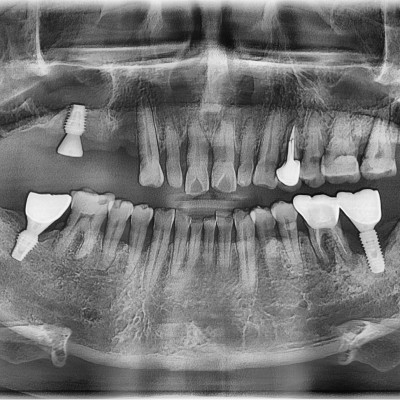

임플란트 재수술 #44.45.46.47 타원 임플란트 보철물 제거 후 임플란트 재수술+치조골 이식술 시행하였습니다.